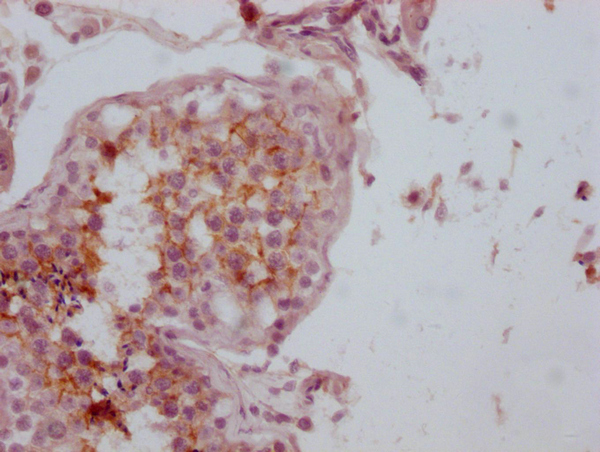

IHC image of CSB-MA153712 diluted at 1:100 and staining in paraffin-embedded human testis tissue performed on a Leica BondTM system. After dewaxing and hydration, antigen retrieval was mediated by high pressure in a citrate buffer (pH 6.0). Section was blocked with 10% normal goat serum 30min at RT. Then primary antibody (1% BSA) was incubated at 4°C overnight. The primary is detected by a Goat anti-mouse IgG polymer labeled by HRP and visualized using 0.05% DAB.